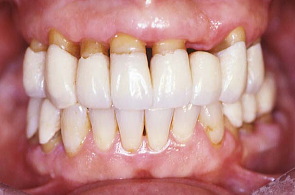

矯正も兼ねて仮歯を修正:歯と歯の隙間を閉じる為仮り歯を修正したところ。患者は健康になり笑顔を取り戻した。日常の話やいろいろな悩みを聞いているうちに大分治療に慣れてきたように感じた。 そして物事をポジティブに考えられるようになってきたということだった。この頃から患者は体の調子を整える為、食事のダイエットを初めた。

半年後位だったと記憶、初診の頃より約10Kgも痩せ、身体も歯ぐきも健康を取り戻していた。笑顔を忘れていた表情も性格も見違えるほどに明るくなっていた。

さっそく私は、グラビアに写っている女性と同じ歯の形を仮り歯で再現した。患者はとても喜んでくれた。また一段と笑顔が綺麗になったように感じた。

口元と上の歯の仮り歯を拡大して撮影したところ。奥のほうの歯は義歯を入れる予定。